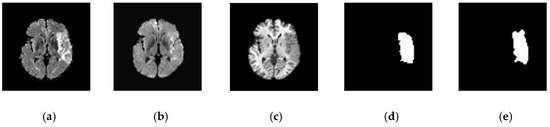

2.2. Image Database

2.3. VGG-SegNet

2.4. Image Features